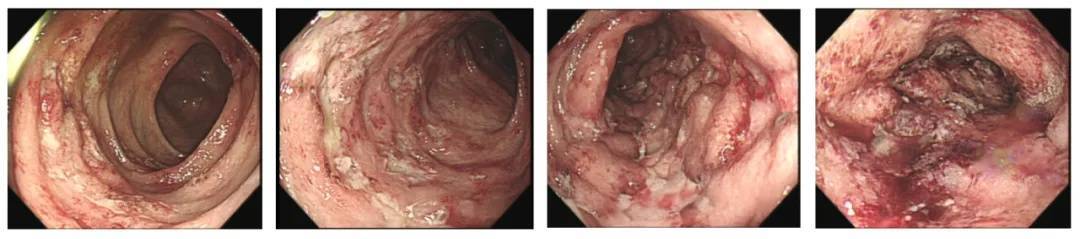

镜下所见

施主任详细询问病史后,敏锐的察觉小贺的症状不简单。随后,施主任立刻为小贺完善了肛瘘磁共振、肠镜、胶囊内镜等相关检查,组织风湿免疫肾病科、放射科、病理科、营养膳食科等多学科专家联合会诊,最终明确小贺患的是“克罗恩病”。

明确诊断后,施主任团队为小贺制定了以生物制剂为核心的中西医结合治疗方案。经过一段时间治疗,小贺不但血便消失,肠镜下的溃疡、糜烂也明显好转,同时,强直性脊柱炎、虹膜炎、肛瘘等问题也得到了有效控制。

施琳琳主任说道,克罗恩病可以影响消化道的任何部位,但最常累及的部位是回肠末端,病变呈一个跳跃式的改变,病变的黏膜之间可以有正常的黏膜。有时候还会累及到胃肠道以外的器官,比如出现肛瘘、肛周脓肿、口腔溃疡、皮肤结节性红斑、关节炎和虹膜炎等,因此诊断有较高的难度。